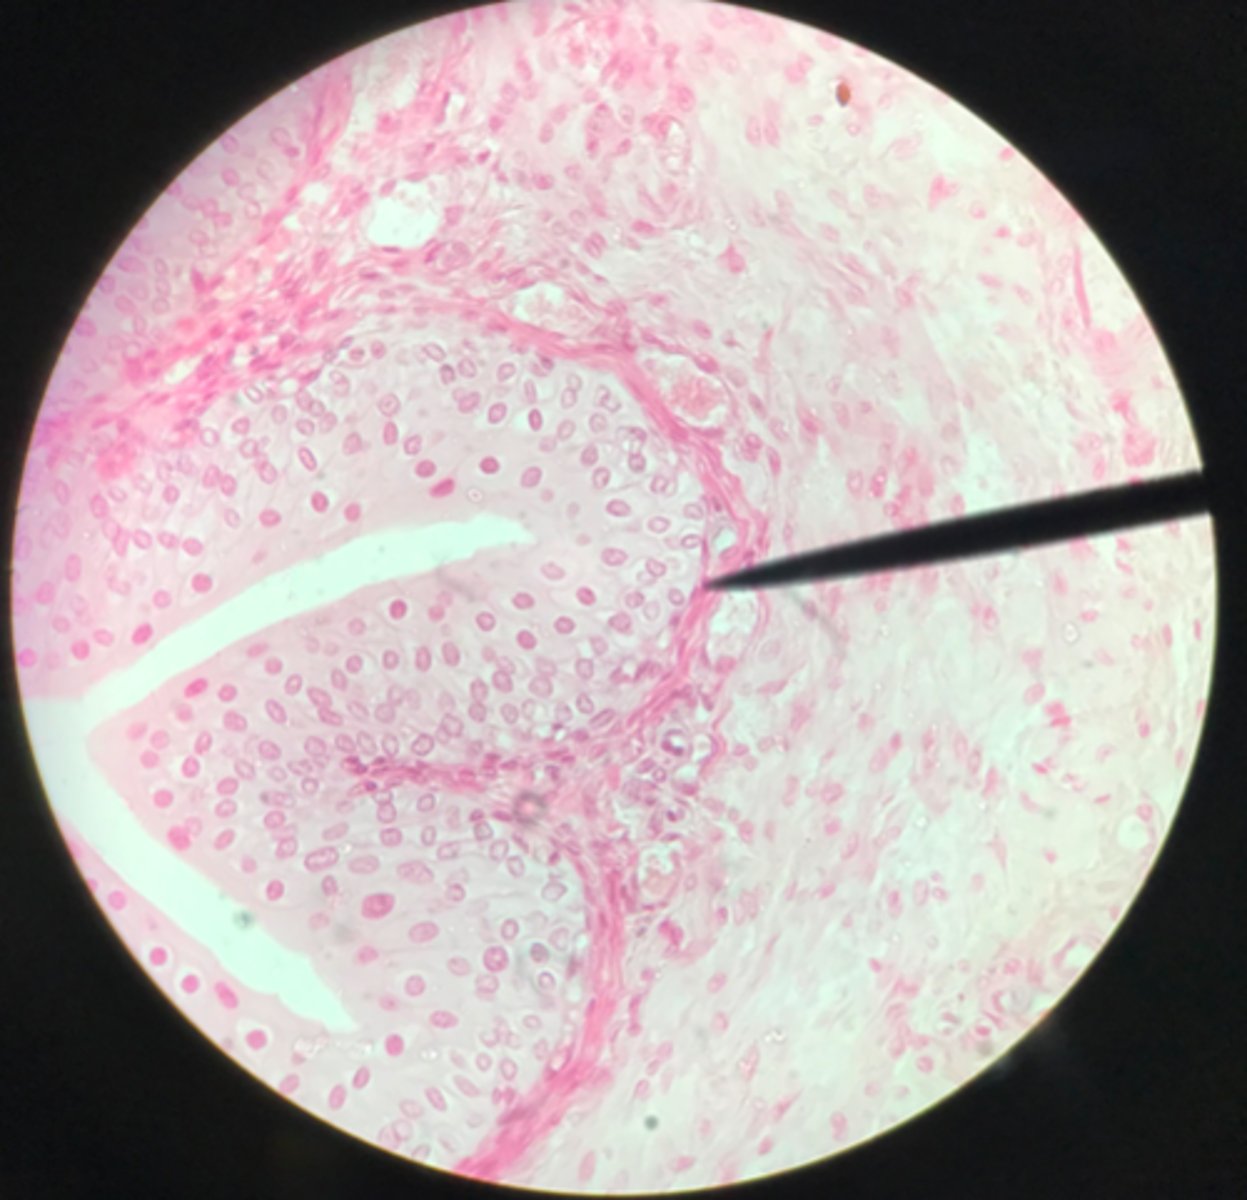

Transitional epithelium of the bladder

What tissue is depicted on the slide above the pointer?

Basement membrane

What cells of transitional epithelium are located where the pointer is at?

Ureter

Transitional epithelium

What structure/organ is depicted on this microscope slide?

What tissue makes up a majority of it?

Transitional epithelium

What type of tissue makes up the inner lining of the ureter?

Ureter

Note the smooth muscle layer surrounding the transitional epithelium

What organ is depicted on this slide?